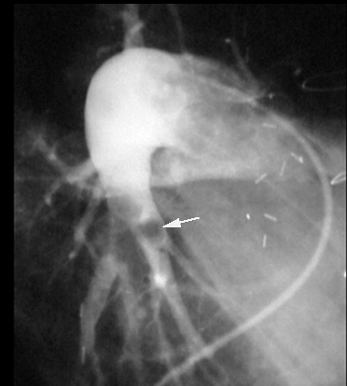

Pulmonary Angiogram: Pulmonary Embolus

Arrow points to filling defects.